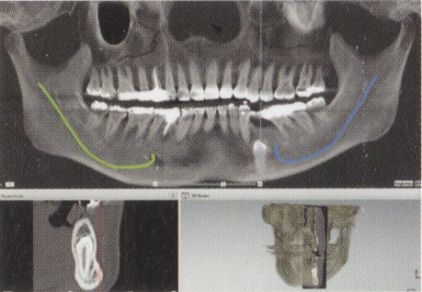

当院の安全への取り組み①CTによる診査診断

CT撮影を行い、神経、血管、骨などの状態を立体的に把握します。

当院の安全への取り組み②サージカルガイドによる埋入

コンピューターで治療計画を立てます。

インプラントの埋め込む角度やサイズ、深さ等を事前にシミュレーションします。

治療にかかる費用や期間なども算出しお伝えいたします。

治療計画に基づき治療を開始します。

シミュレーション時に設計した情報に基づき作成したサージカル・テンプレートというガイドをお口に取り付け、インプラントを埋入します。